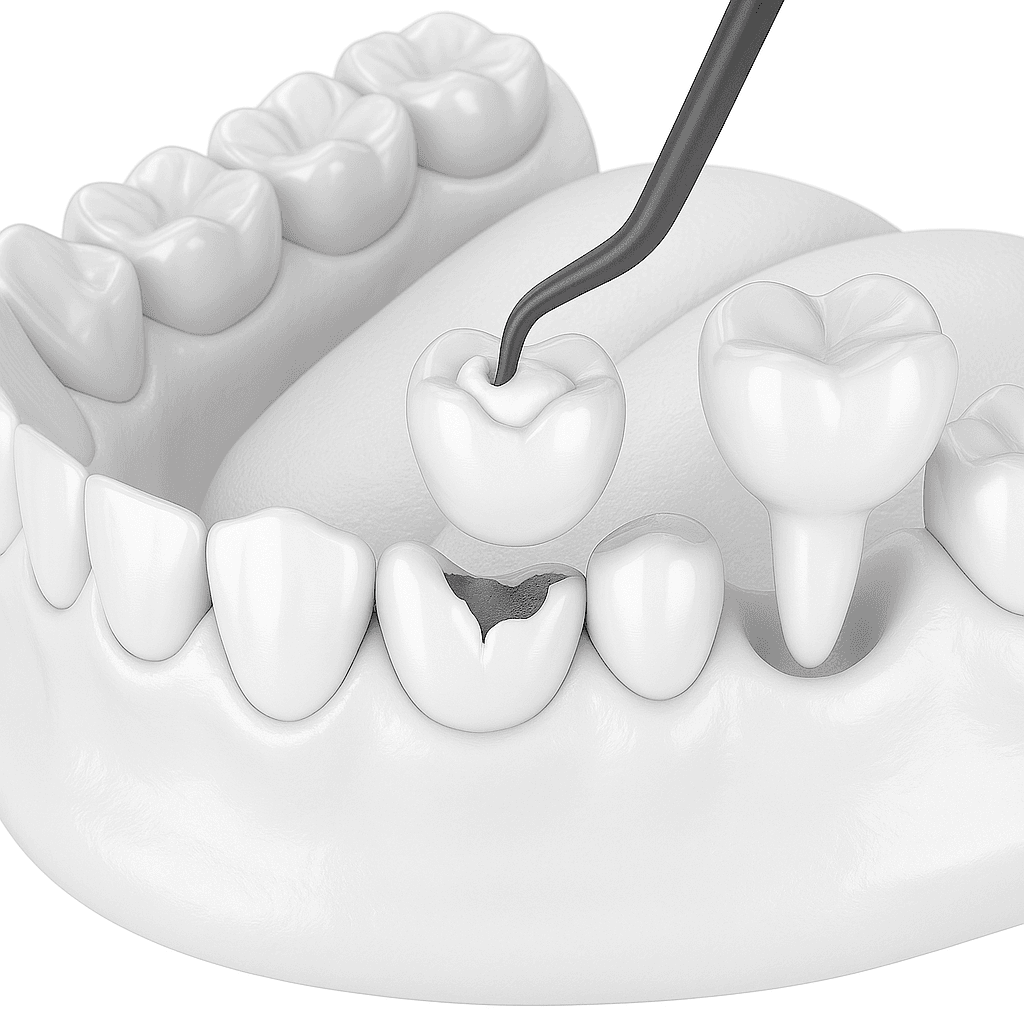

- • Proces leczenia obejmuje diagnostykę, zabieg chirurgiczny, gojenie oraz zamocowanie korony, mostu lub protezy.